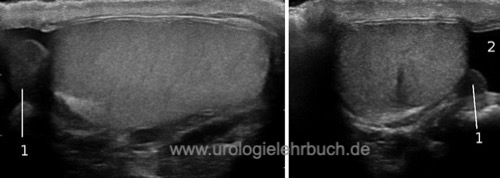

der Hoden zeigt ein homogenes Echomuster, die Tunica albuginea stellt sich dünn echogen dar. Die strahlenförmige Anordnung der Lobuli testes lässt sich erahnen. Der Nebenhoden ist eindeutig vom Hoden abgrenzbar [Abb. Sonographie des Hodens].